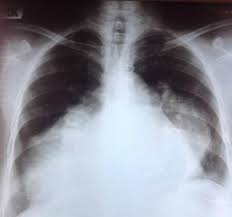

Peripartum Cardiomyopathy The Bmj

Peripartum Cardiomyopathy The Bmj from www.bmj.com

Peripartum Cardiomyopathy Circulation

Peripartum Cardiomyopathy Circulation from www.ahajournals.org